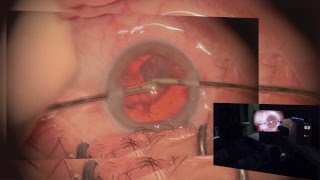

Heads up 3D video in a cataract surgery and vitrectomy video

Heads up 3D video in a cataract surgery and vitrectomy

Heads up 3D video in a cataract surgery and vitrectomy What is a vitrectomy? (3D Animation)

What is a vitrectomy? (3D Animation) Ngenuity 3D heads up surgery , cataract Lukan Mishev Live Stream